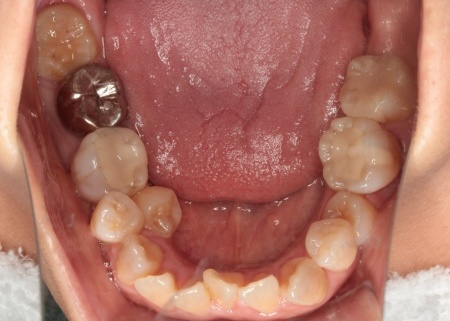

治療中

歯を移動させるスペースを確保する目的で、右上第1小臼歯、右下第2小臼歯、左下第2小臼歯の計3本と、温存が難しい右下第2大臼歯1本、合計4本の歯を抜きます。

温存が難しい右下奥歯を抜いたあとは、その後方にある親知らずを手前に移動させることで、機能面の改善と歯の寿命延長が期待できることを説明しました。

また、銀歯が装着されている歯を抜くことで下の歯がすべて白くなり、見た目の印象が改善されることも併せてお伝えしています。

まずは、治療計画に沿って計4本の歯を抜きます。

後日抜歯時の傷が治癒したことを確認し、ワイヤー矯正を開始しました。